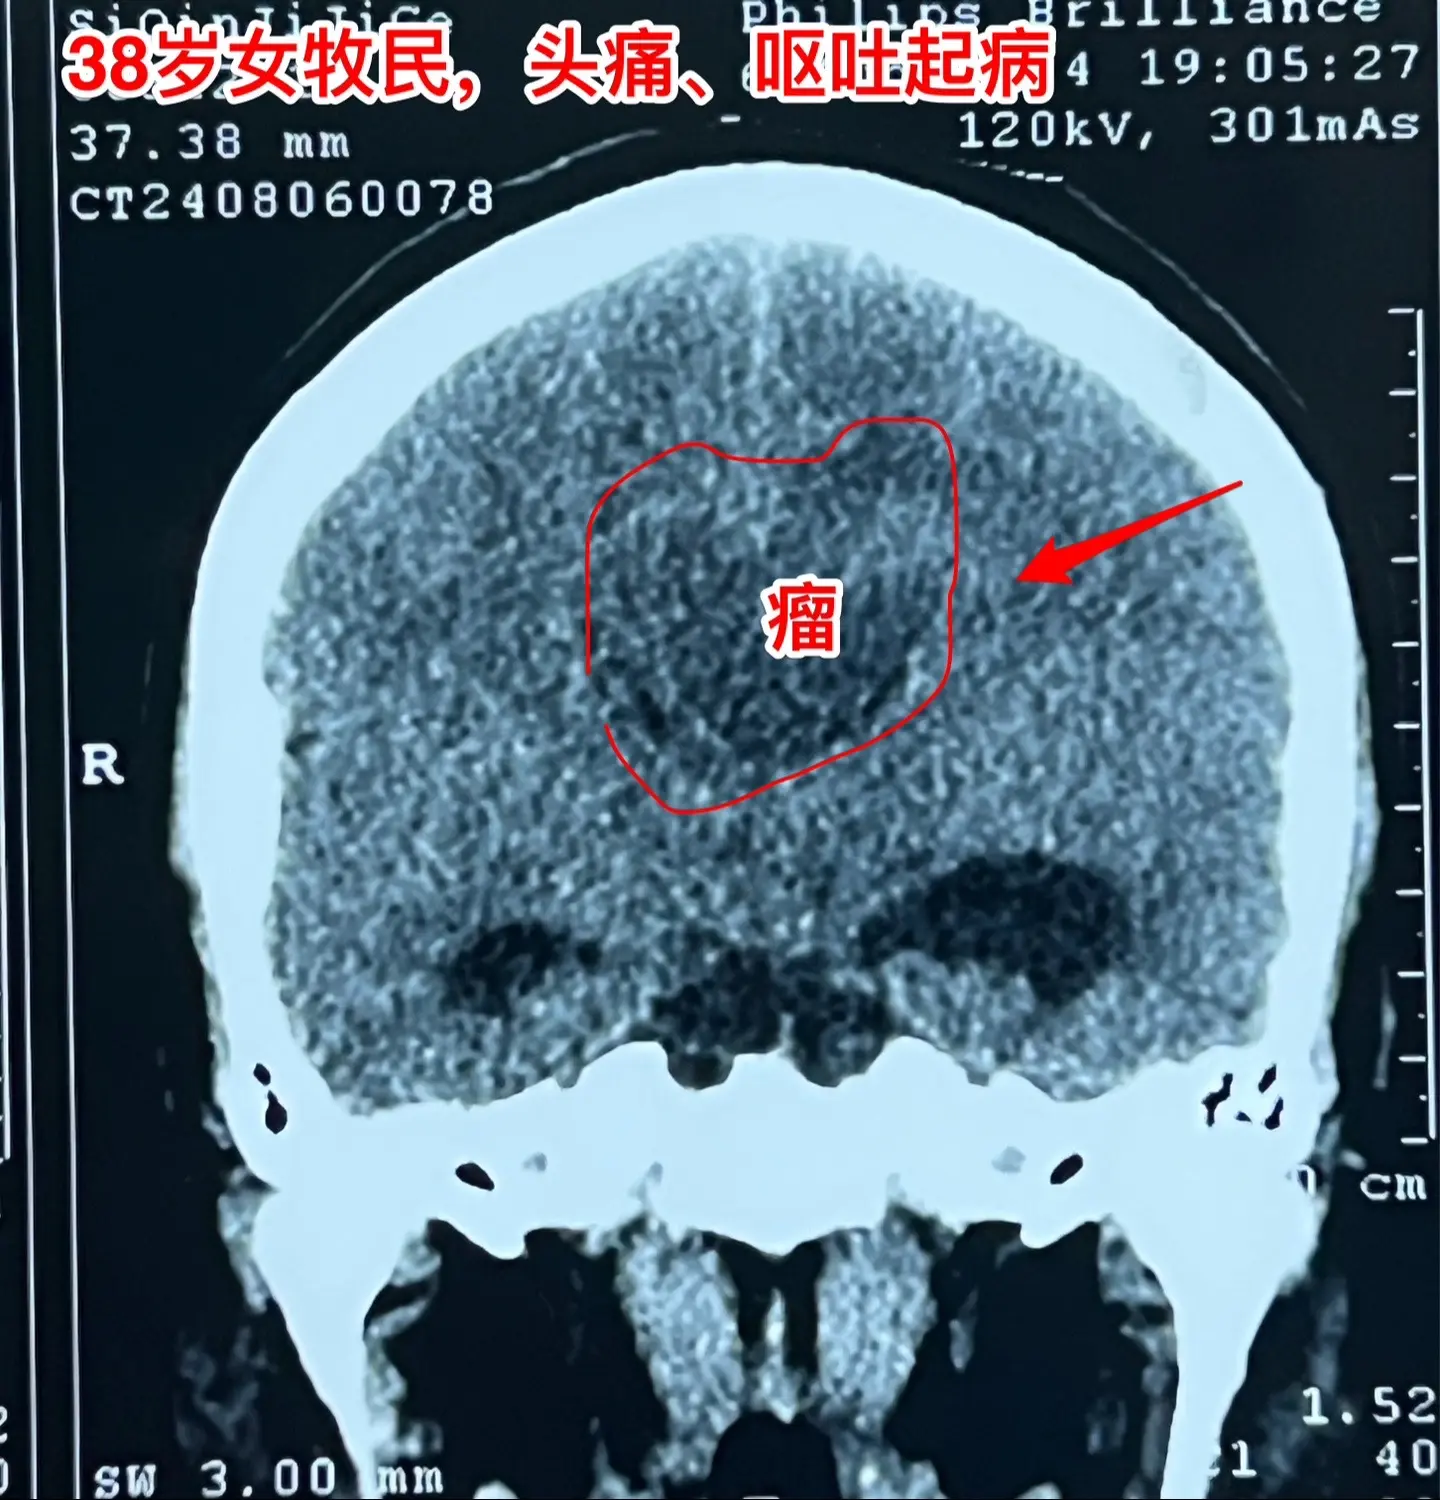

38岁女性脑部发现肿瘤、平时心跳很慢。38岁女性,西乌珠穆沁旗牧民,因头痛、呕吐10天,在锡林浩特市检查发现脑部肿瘤,遂到北京三博脑科医院来作手术。 脑部肿瘤见图,考虑是胶质瘤,肿瘤起源于胼胝体,胼胝体受肿瘤侵蚀,手术前病人的语言和智能没有明显障碍。 在手术准备过程中,发现 病人的心跳很慢,平常才41次/分,夜间最慢慢到31次/分。诊断为窦性心动过缓,为了确保手术安全,不得不临时安放心脏起搏器。 8月9日顺利完成肿瘤切除手术。手术过程很顺利。术中快速冰冻病理报告为胶质母细胞瘤。术后病人很快就清醒了。术后四肢活动无障碍,语言能力和智能情况需要详细评估。